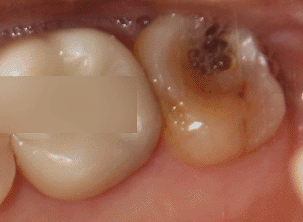

하단 예시 사진을 관찰해보면

심하게 썩어 있는 최후방구치(# 27)을

확인할 수 있습니다.

이미 치관 부위 부식이 일어나

깨져 있는 것을 볼 수 있습니다.

위쪽 맨 뒤에 있는 어금니에 위치해 있기에

문제가 생기면 쉽게 알아차리기

어려운 편에 속합니다.